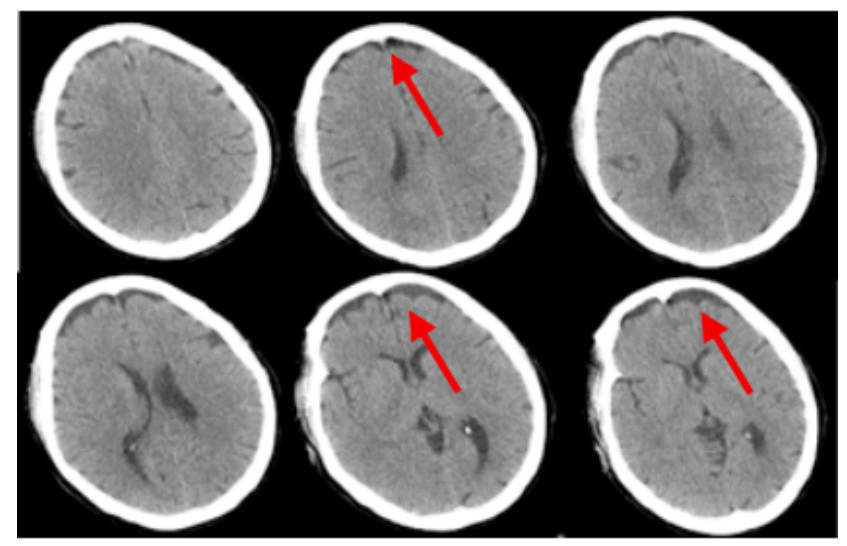

2 结果入院时实验室查急诊血清胆碱酯酶(cholinesterase, ChE):小于196 U/L。血常规:白细胞(white blood cell, WBC)9.24×109/L,中性粒细胞百分比(neutrophil, NEUT%)88.3%,PLT 230×109 /L,红细胞(red blood cell, RBC) 4.08×109/L血红蛋白(hemoglobin, Hb)128 g/L。动脉血气分析:酸碱度(potential of hydrogen, pH)7.247,二氧化碳分压(partial pressure of carbon dioxide, PCO2)30.2 mmHg,氧分压(partial pressure of oxygen, PaO2)93.8 mmHg(呼吸机辅助通气下吸氧浓度为50%),氧合指数284.3%,血钠(Na+) 141.1 mmol/L,血钾(K+) 3.25 mmol/L,乳酸(lactic acid, Lac)8.35 mmol/L,血糖16.05 mmol/L,碳酸氢根12.8 mmol/L,碱剩余-13.2 mmol/L。床旁快速心肌酶:心脏特异性肌钙蛋白Ⅰ(cardiac troponin, cTnⅠ)0.17 ng/mL,肌红蛋白(myoglobin, Myo)123.6 ng/mL,肌酸激酶同工酶(creatine kinase, myocardial-type, CK-MB)17.83 ng/mL。床旁NT-proBNP: 106 ng/L,肝功能:天门冬氨酸氨基转移酶(aspartate aminotransferase, AST)162 U/L,丙氨酸氨基转移酶(alanine aminotransferase, ALT)86 U/L,肌酸激酶196 U/L,乳酸脱氢酶(lactate dehydrogenase, LDH)302 U/L。肾功能:肌酐(creatinine, CREA)104 μmol/L,尿素氮4.84 mmol/L。凝血常规:PT 12.9 s,APTT 34.7 s。新冠病毒抗体阴性。急性感染三项:白介素6 1 148.0 pg/mL,降钙素原(procalcitonin, PCT)0.688 ng/mL,超敏C反应蛋白0.78 mg/L。后期上述指标变化见图 1。床旁胸片显示,(1)双肺纹理增多、增粗、模糊,双肺感染可能;(2)左侧胸腔少量积液可能。见图 2。住院期间讨论CT示:硬膜下积液,见图 3。

| 注:2022-07-21头颅CT示硬膜下积液,如红色箭头所示 图 3 患者住院期间头颅CT结果 |

因此,笔者对本病例甲维虫螨腈和毒死蜱混合农药中毒的救治成功经验进行分析与总结:⑴减少毒物的吸收:本患者送至我院时已长达4 h,依然可闻及刺鼻农药味,且患者具体服用甲维虫螨腈和毒死蜱的剂量和时间不详,我们根据急性中毒的治疗原则,给予患者床旁清水洗胃2次,每次洗胃10 000 mL,两次洗胃间隔8 h,洗胃后未闻及刺鼻农药味和洗胃液已清澈无未,予以暂停洗胃。此外,洗胃后均给予20%甘露醇+活性炭30 g注入胃管导泻,同时并嘱患者家属给患者擦洗全身(包括头发)并更换干净衣服。⑵促进毒物排泄:除补液利尿外,应尽早血液净化,首选血液灌流[3],也可血液灌流联合其他血液净化方式是虫螨腈中毒救治成功的重要手段[10, 13, 17],但目前无大样本研究数据支持。本患者分别在入院2 h、4 h行血液灌流2次,入院29 h行床旁CRRT-CVVH治疗,期间更换2次滤器,总共治疗62 h,这与孟娜等[18]的研究一致。患者床旁CRRT上机时间稍延迟,分析其原因是因患者在行血液灌流6 h后出现全身多处渗血,且患者血小板较入院时明显下降,凝血四项出现异常,考虑可能与血液灌流时使用肝衰泡灌、低分子肝素抗凝时剂量过大有关,但也不排外中毒所致多器官损伤引起出凝血机制异常。⑶药物治疗:有特效解毒剂的农药尽量早期足疗程足剂量使用,然后根据其中毒机制选用特定有用的药物治疗。本患者服用的毒死蜱为有机磷农药,且本患者所服两种农药均为脂溶性,我们早期就给予脂肪乳吸附治疗是有效的。但Furubeppu团队[19]在虫螨腈中毒患者中应用脂肪乳后未能遏制患者病情进展,而脂肪乳应用在犬虫螨腈中毒[20]和人毒死蜱中毒[21]上是可以遏制病情进展的。除此之外,本例患者早期还应用了乙酰半胱氨酸、维生素抗氧化,给细胞提供一定的保护作用,与Chomin等[22]研究一致,且指南共识也推荐[3]。⑷其他对症支持治疗:综合治疗很重要,如出现发热,予以物理降温、冰毯、退烧药等使用;昏迷患者应早期给予甘露醇/甘油果糖脱水降颅压,控制脑水肿;出现呼吸循环衰竭,予以呼吸机辅助通气以及补液、升压药物的应用。本患者入院8 h就出现高热,体温高达41℃,且住院期间持续存在发热,体温波动在37.4~41.5℃,当时PCT、WBC、NEUT%均升高,考虑住院期间持续间断发热可能与与使用解毒剂肟类复能剂(碘解磷定)、甲维虫螨腈中毒本身和感染三方面因素有关。因此大大增加了治疗者判断与评估病情的难度,同时也是对主管医生的挑战,在这样的情况下治疗者需要对到底是哪种因素所致高热而作出准确判断。另外本患者被发现时就已经出现意识障碍,而虫螨腈中毒和重度毒死蜱中毒均会引起意识障碍,这就需要治疗者综合考虑、综合治疗,入院后救治团队立即给予甘露醇、甘油果糖脱水降颅压治疗对脑组织进行保护,在本患者的治疗是有效的。除此之外,本患者在入院72 h后双下肢及口周出现不自主抖动,同时颜面部可见出汗,考虑为毒死蜱所致的烟碱样症状和毒蕈碱样症状,但也不排除甲维•虫螨腈引起迟发型毒性反应所致抽搐和出汗[17]。有报道[3]虫螨腈中毒可致头颅MRI异常,主要为脑白质病变或脱髓鞘病变。遗憾的是本文所报道患者住院期间未进一步完善头颅MRI检查,期间仅在入院140 h(第6天)外出完善头颅CT一次后示双额部颅骨下条片状液体密度影,考虑硬膜下积液(见图 3),后期就未予重视及复查。分析其主要的原因是笔者对甲维虫螨腈中毒所致的迟发型毒性反应(神经系统症状)认识不够充分,且在治疗期间治疗团队大部分时间可能关注在毒死蜱中毒时解毒药的应用是否足量,而忽略了虫螨腈所致的迟发型毒性反应的严重性。